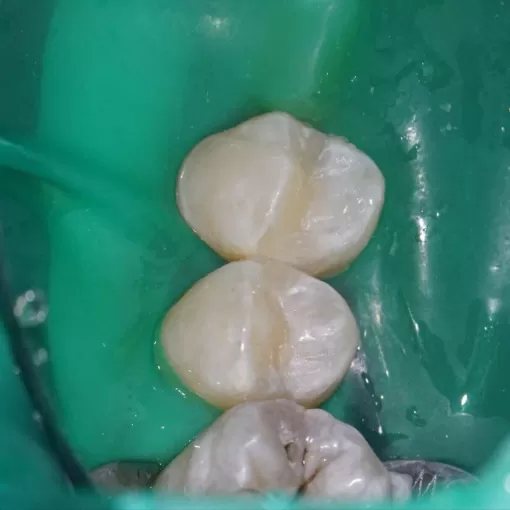

Эстетическое восстановление 46,47

Эстетическое восстановление 46, 47

Кариес зубов 24, 25. Скрытый при осмотре без бинокуляров и микроскопа. В области тёмных фиссур (бороздок на жевательной поверхности) и на боковых поверхностях.

Реставрация композитом. Правильная форма - залог правильной функции.